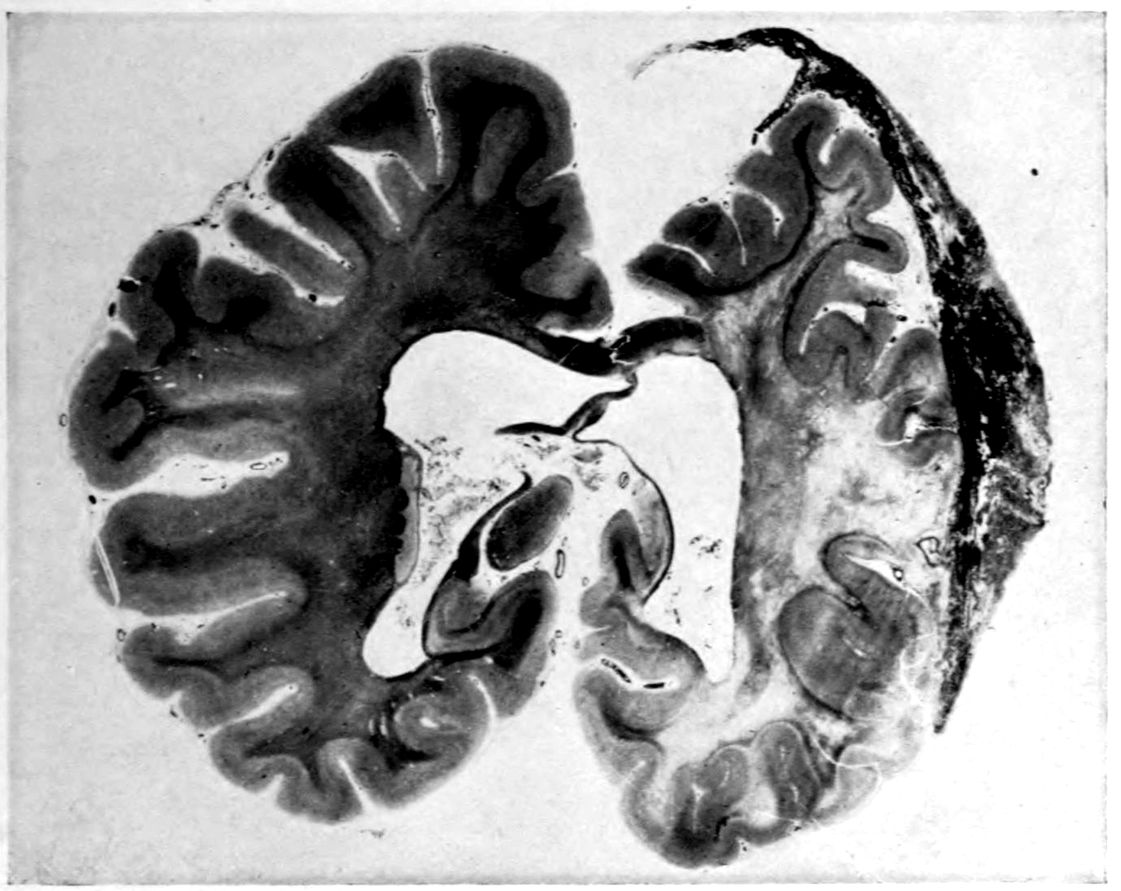

The autopsy findings were as follows:

Head: Calvarium of moderate thickness; diploë present; dura slightly adherent over bregmatic region. Longitudinal sinus contains cruor clot. Dura is somewhat thickened and slightly more opaque than normal. Pacchionian granulations, small but fairly numerous. Pia contains throughout a considerable excess of clear 44serous fluid. The convolutions in general are of good breadth and proportion. There is an atrophic area roughly circular in outline and about 2 cm. in diameter in the posterior part of the right third frontal convolution corresponding to Broca’s area on the opposite hemisphere. The space thus formed is filled with edema held by the pia. On the left side is a similar subpial collection which covers the site of the posterior portions of all of the third frontal convolutions, parts of the lower end of the precentral convolution, and the whole of the first temporal convolution, which have disappeared entirely. The basal vessels show slight changes.

Cerebellum and basal ganglia are grossly normal.

The spinal membranes are negative. The regions of the pyramidal tracts in the cord are firm, project slightly from surface of section, and are china white.

Summary: Here is a picture made up almost purely of Vascular Neurosyphilis, with Secondary Spinal (Pyramidal Tract) Changes. Doubtless the genesis of this picture is allied to that of Case 1 (Alice Morton) and to that of the terminal vascular complications in a tabetic, Case 2 (Francis Garfield).

Vascular neurosyphilis—effects of syphilitic thrombosis of Sylvian artery 10 years before death. (Case 4.)

Case 4. (See previous figure for brain lesion.) Three levels of the spinal cord showing unilateral pyramidal tract sclerosis, 10 years after cerebral thrombosis.